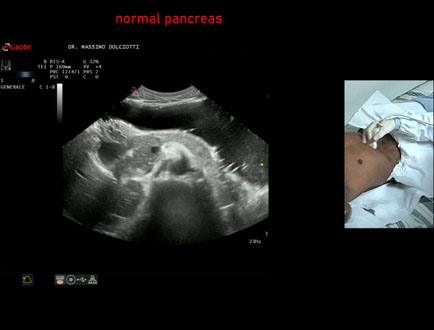

Data inserimento: 05/12/2024

Ecografia del: 28/11/2024

Strumento: Esaote MyLab Eight

Sonda: Convex Multifrequenza 1-8 MHz

Età Paziente: M 20 anni

Motivazione dell'esame: dolori addominali.

Commento all'esame: le immagini ed il video documentano il pancreas di ecostruttura e morfovolumetria regolare, con aspetto ipoecogeno, ben evidenziate la regione cefalica, il corpo e la coda.

Conclusioni: pancreas di ecostruttura e morfovolumetria regolare (pancreas with regular echostructure and morphovolumetry).

Presentazione: Dr. Massimo Dolciotti - Ancona

Elaborazione digitale: Andrea Dini - Ancona